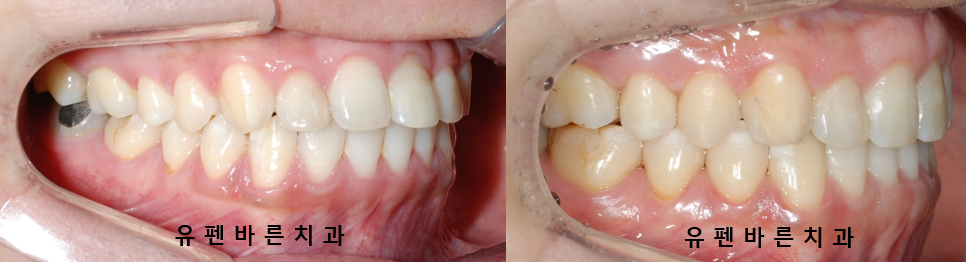

인비절라인 라이트로 단 28개의 장치를 통해 앞니의 뻐드러진 각도가

많이 개선되었습니다!

좁았던 악궁이 점점 확장되면서

뻐드러져 있던 앞니들이 안쪽으로 들어가고

맞닿고 있던 위아래 치아들이 제 위치를 찾았을 뿐만 아니라

입이 살짝 들어가 보이는 효과까지 얻을 수 있었습니다.

인비절라인을 통해 앞니의 접촉면을 최소화 하면서

치아의 심미적인 요소 뿐만 아니라 기능적인 요소 또한 개선시킬 수 있었어요. :)